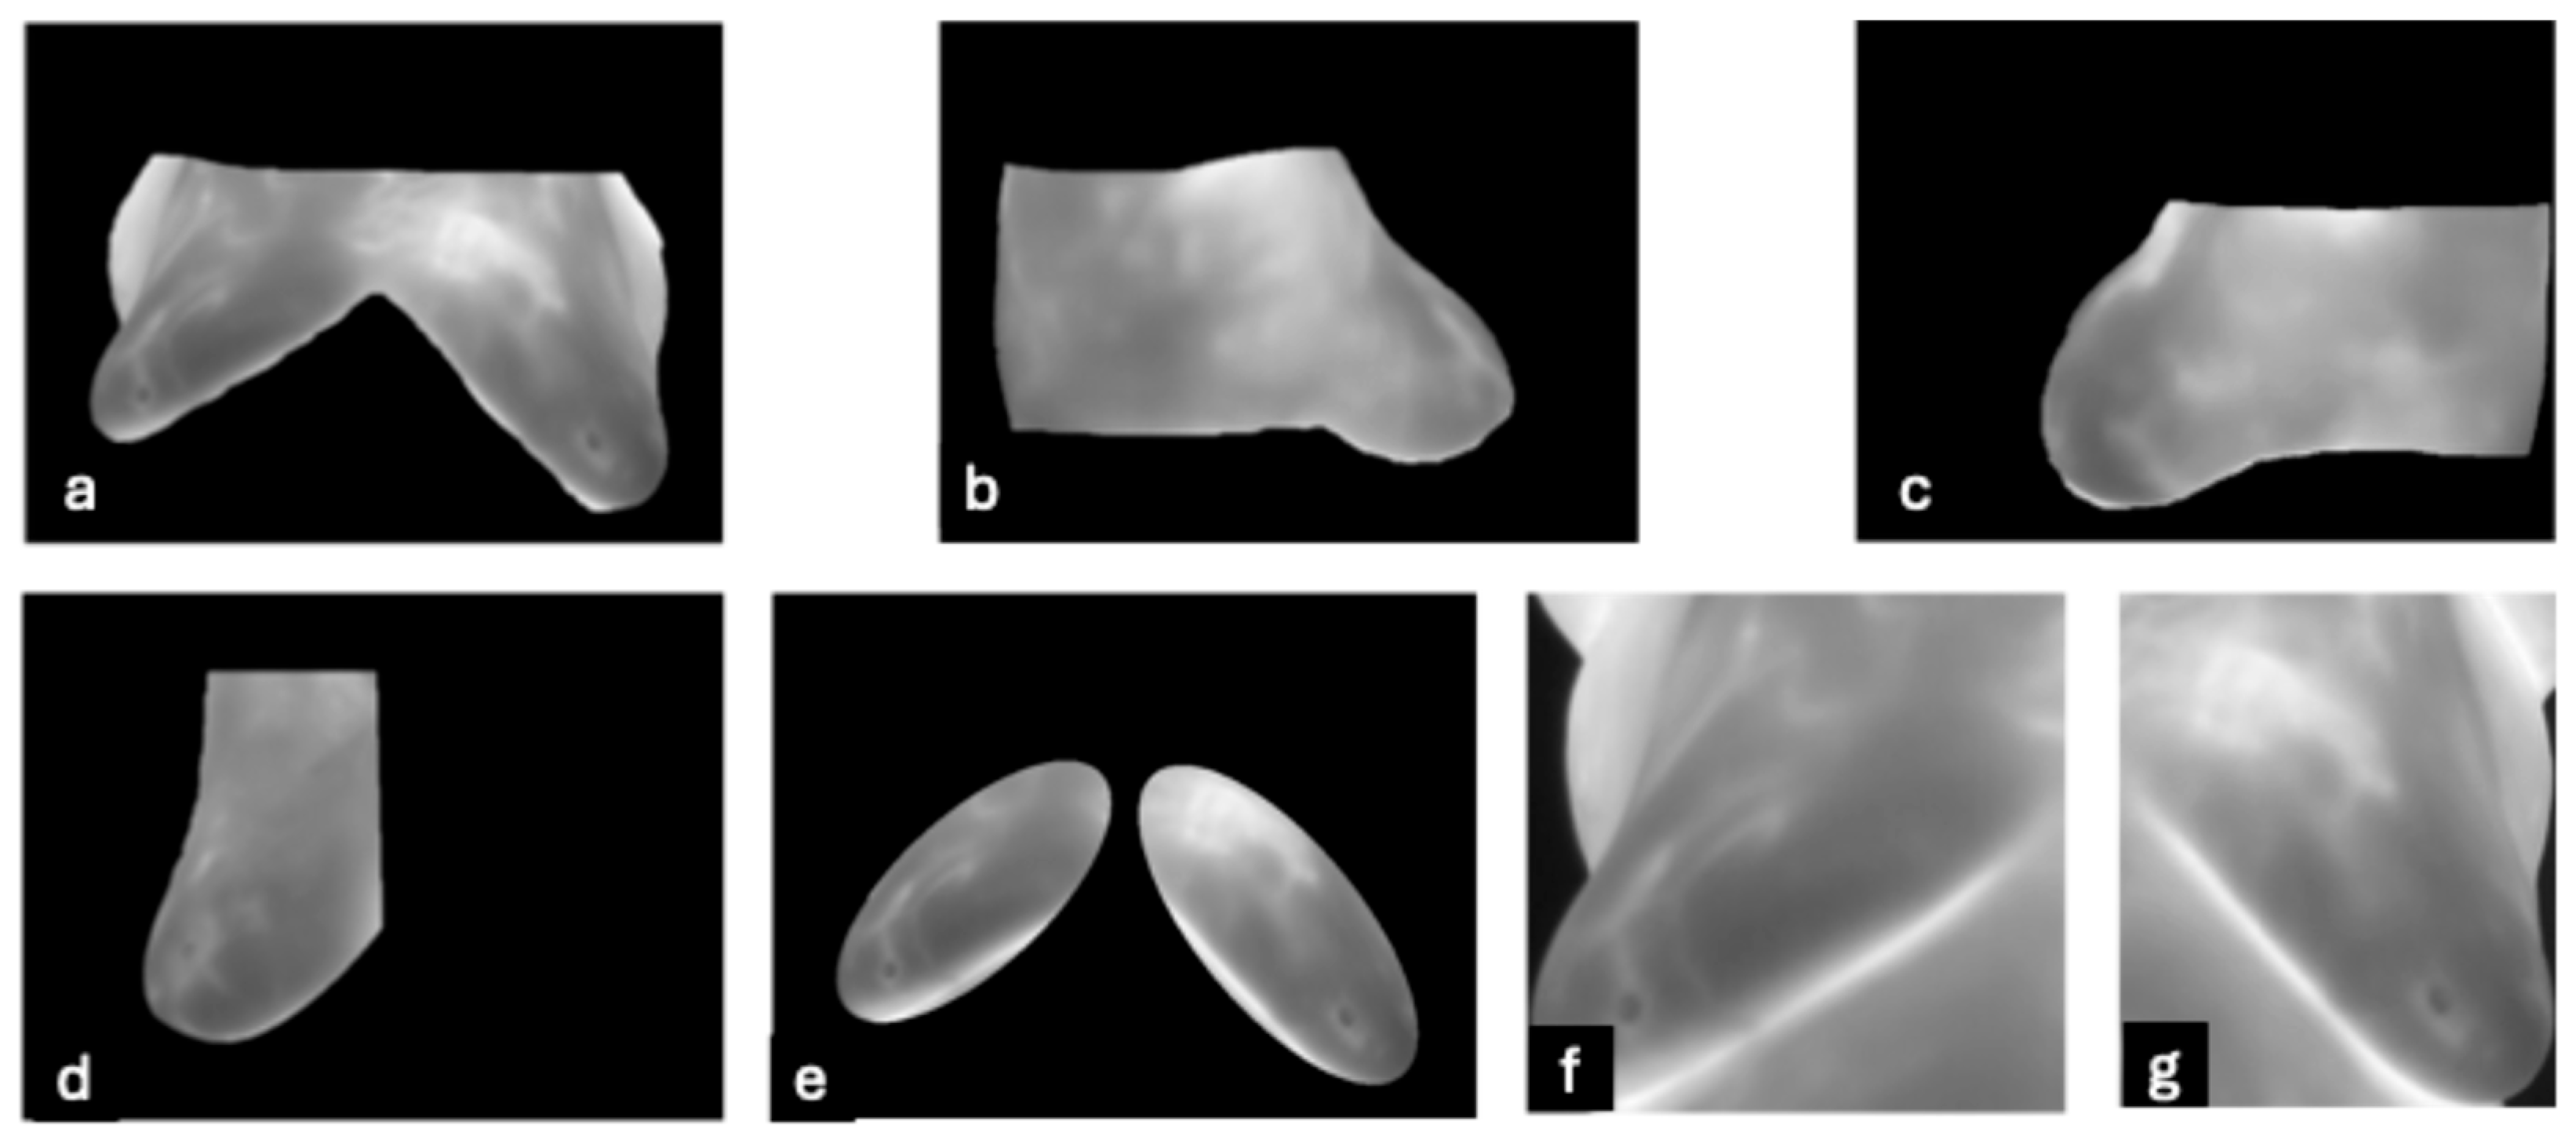

- DMR-IR Dataset: The Database for Mastology Research Infrared (DMR-IR) dataset [39] is the most widely used database in research studies. Of the 26 studies covered in this review, 20, 77%, used this dataset. The DMR-IR dataset includes infrared (IR) images, several digitized mammograms, several ROI masks, and clinical data for 293 patients captured at the Hospital Universitario Antonio Pedro (HUAP) of the Federal University Fluminense. The use of this dataset was approved by the Ethical Committee of the HUAP and registered with the Brazilian Ministry of Health under number CAAE: 01042812.0.0000.5243 and is publicly available at http://visual.ic.uff.br/dmi/, accessed on 6 April 2025. Infrared images are captured using Static Image Thermography (SIT) and Dynamic Image Thermography (DIT) described in [19]. The database also includes segmented images for 56 patients (37 sick and 19 normal). Figure 4 shows sample images from this dataset.